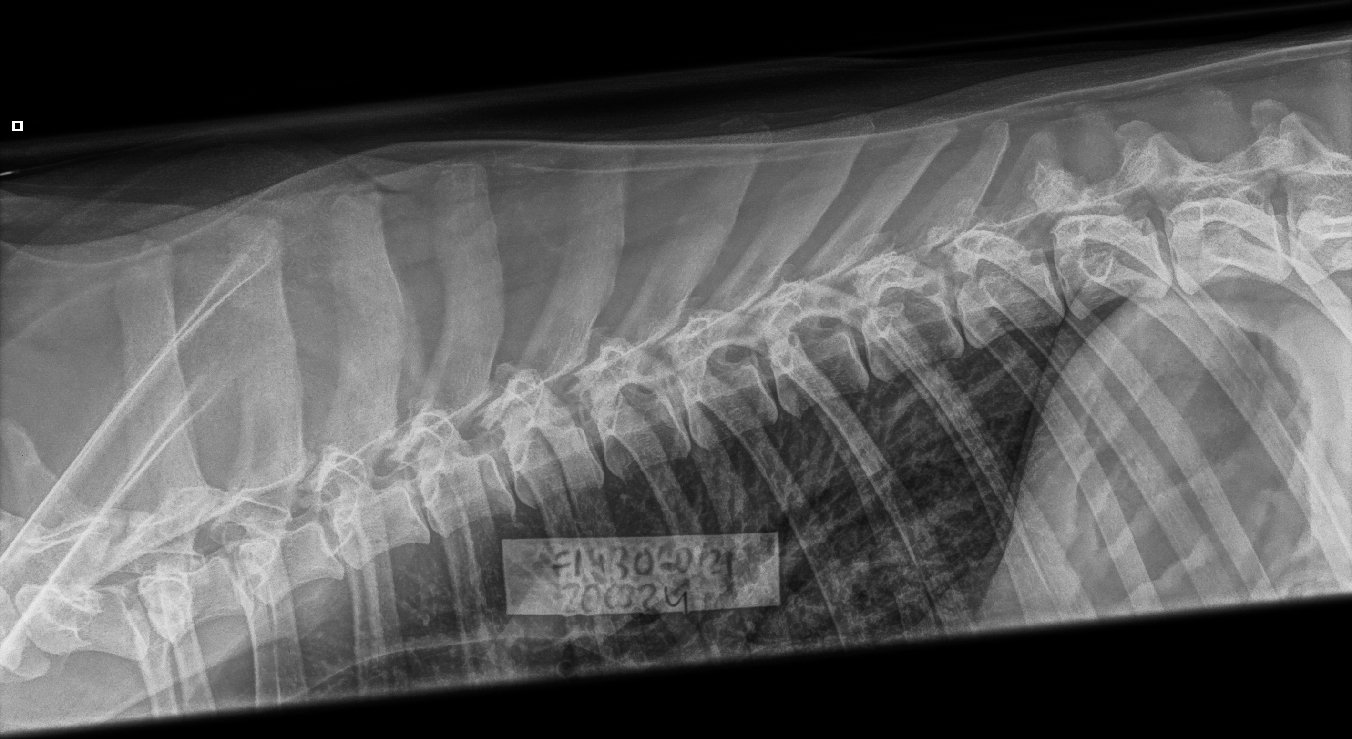

Olen röntgenkuvauttanut tanskandoggieni selät 2010 vuodesta lähtien lonkka- ja kyynäräkuvien ohessa. Näistä lonkka- ja kyynäräkuvat ovat pakolliset rekisteröinnin kannalta, selkäkuvaus ei. Kahdella koirallani on todettu jo nuorena spondyloosi eli selkärangan rappeuma mikä voi aiheuttaa suurta kipua ja heikentää oleellisesti sen elämänlaatua. En rasittaisi selkäsairasta narttuani pennutuksella, jonka vuoksi haluan selän aina myös tutkia. Toisekseen uskon että alttius sairastua ko. sairauteen on jossain määrin perinnöllinen. Pentueen molemmat vanhemmat on kauttaaltaan kuvattu ja virallisesti lausuttu. Emällä täysin puhdas selkä, isällä lievä aste 1 spondyloosin osalta, mutta eläinlääkärin sanoin terve selkä.